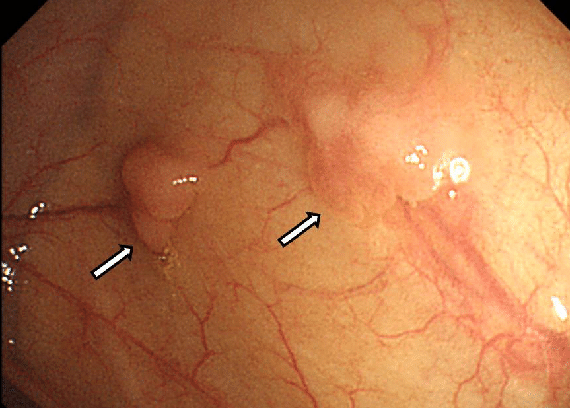

Стрелки указывают на полипы толстой кишки